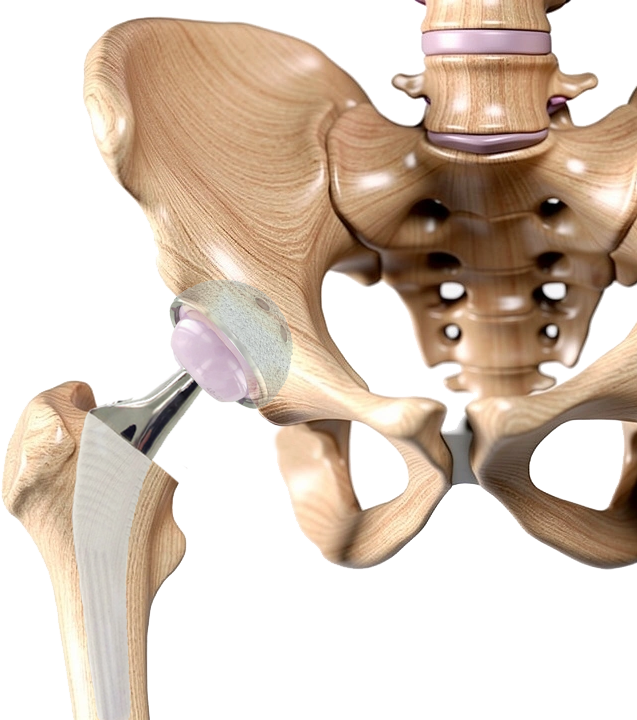

Cadera

Conoce el reemplazo protésico de cadera.

La prótesis de cadera reemplaza las piezas desgastadas en el fémur y en el acetábulo. Existen muchos componentes o piezas diferentes, que el cirujano puede escoger para configurar una cadera.